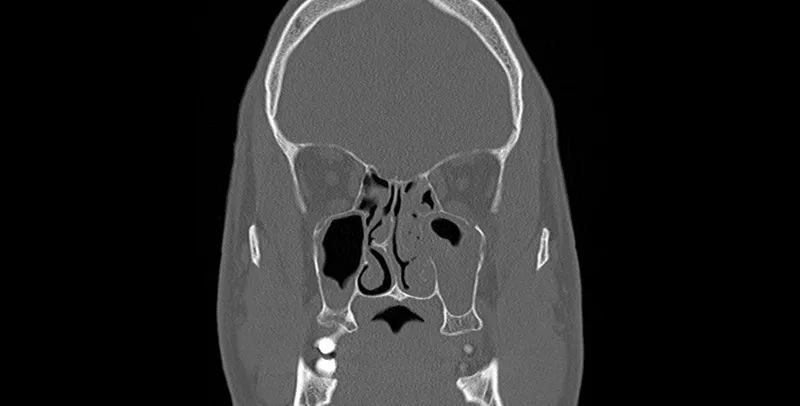

Image of the disease chronic sinusitis and other variables